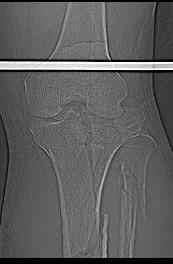

Пациенту сделали КТ - ухитрились сделать на шине Белера (не давал положить прямую ногу) - срезали передний отдел. Планируется на пятницу (24.12) на операцию - синтез длинной мыщелковой LCP-пластиной Synthes :). Отек ближе к слову умеренный (окружность голени +4 см по сравнению со здоровой). КТ и снимок на вытяжении прилагаются.